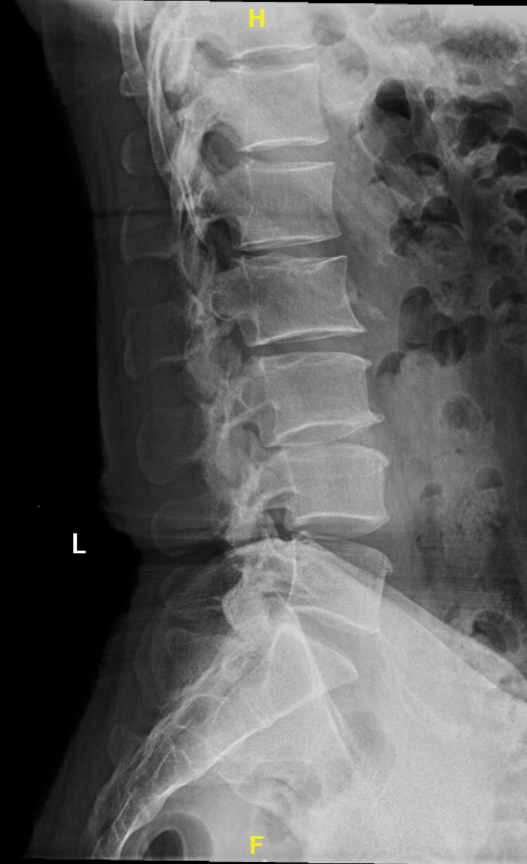

2018-11 术前腰椎正侧位X线片显示:较明显的退行性改变和脊柱侧弯,故指导患者进行小燕飞、伸懒腰、吊单杠等腰背肌和脊柱骨质锻炼

2020-01 术前腰椎正侧位X线片显示:较明显的退行性改变和脊柱侧弯,故指导患者进行小燕飞、伸懒腰、吊单杠等腰背肌和脊柱骨质锻炼